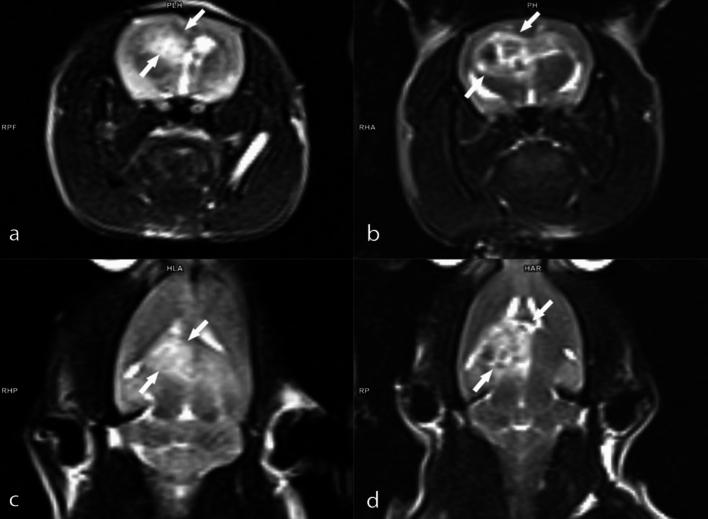

Limited advancements in managing malignant brain tumors have resulted in poor prognoses for glioblastoma (GBM) patients. Standard treatment involves surgery, radiotherapy, and chemotherapy, which lack specificity and damage healthy brain tissue. Boron-containing compounds, such as boric acid (BA), exhibit diverse biological effects, including anticancer properties. This study aimed to examine whether boron supplementation, as BA, can inhibit glioblastoma growth in a xenograft animal model. Using MRI-based tumor size measurement, survival rates, hematological, clinical biochemistry analyses, and genotoxicity parameters, we assessed the impact of BA. Histopathological, immunohistochemical, and immunofluorescence examinations were also conducted. All BA doses (3.25, 6.5, and 13 mg kg b.w.) extended survival compared to GBM controls after 14 days, with a dose-dependent anti-GBM effect observed in MRI analyses. BA treatment improved hematological (WBC and PLT counts) and biochemical parameters (LDL-C, CREA, and ALP). Histopathological examination revealed a significant reduction in tumor diameter with 6.5 and 13 mg kg BA. Immunohistochemical and immunofluorescence staining showed modulation of intracytoplasmic Ki67, cytoplasmic CMPK2, and GFAP expressions in tumor cells post-BA treatment. Additionally, BA did not increase micronuclei formations, indicating its non-genotoxic nature. In conclusion, targeting tumor suppressor networks with boron demonstrates significant therapeutic potential for GBM treatment.

恶性脑肿瘤治疗进展有限,导致胶质母细胞瘤(GBM)患者预后不良。标准治疗包括手术、放疗和化疗,这些方法缺乏特异性,会损害健康脑组织。含硼化合物,如硼酸(BA),具有多种生物学效应,包括抗癌特性。本研究旨在探讨以BA形式补充硼是否能在异种移植动物模型中抑制胶质母细胞瘤的生长。我们使用基于MRI的肿瘤大小测量、生存率、血液学、临床生化分析和遗传毒性参数来评估BA的影响。还进行了组织病理学、免疫组织化学和免疫荧光检查。与GBM对照组相比,所有BA剂量(3.25、6.5和13mg/kg体重)在14天后均延长了生存期,MRI分析显示出剂量依赖性的抗GBM效应。BA治疗改善了血液学参数(白细胞和血小板计数)和生化参数(低密度脂蛋白胆固醇、肌酐和碱性磷酸酶)。组织病理学检查显示,6.5和13mg/kg BA可使肿瘤直径显著减小。免疫组织化学和免疫荧光染色显示,BA治疗后肿瘤细胞内的胞浆Ki67、胞质CMPK2和GFAP表达发生了变化。此外,BA并未增加微核形成,表明其无遗传毒性。总之,用硼靶向肿瘤抑制网络对GBM治疗具有显著的治疗潜力。